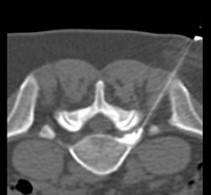

Under computer tomographic or magnetic resonance imaging control, drugs are injected with millimeter precision into the neuralgic points of the spine using fine injection needles. In many patients, this can result in significant pain relief or even freedom from pain. All pain therapy treatments can be carried out on an outpatient basis without any problems due to the low complication rates. A treatment takes a maximum of 10 to 30 minutes.

FacettenblockadeFacet block is a minimally invasive therapeutic procedure for diffuse, motion-dependent non-radicular (not caused by the nerve root) back pain. These complaints are due to wear and tear of the small vertebral joints, caused by wear and tear, poor posture or bending of the spine. These degenerative changes in the small vertebral joints cause approximately 90% of all back pain conditions.

These interventions are CT-assisted, in which a thin special needle is positioned directly on the corresponding nerve plexus (neck, thorax, abdomen, or pelvis) under local anesthesia, and a mixture of local anesthetic and highly concentrated alcohol solution is injected locally. The alcohol solution leads to chemical obliteration of the nerve plexus and thus to pain reduction. The local anesthetic leads to immediate pain reduction when indicated and performed correctly and thus has diagnostic value. For this reason, the procedure is often performed in two stages.